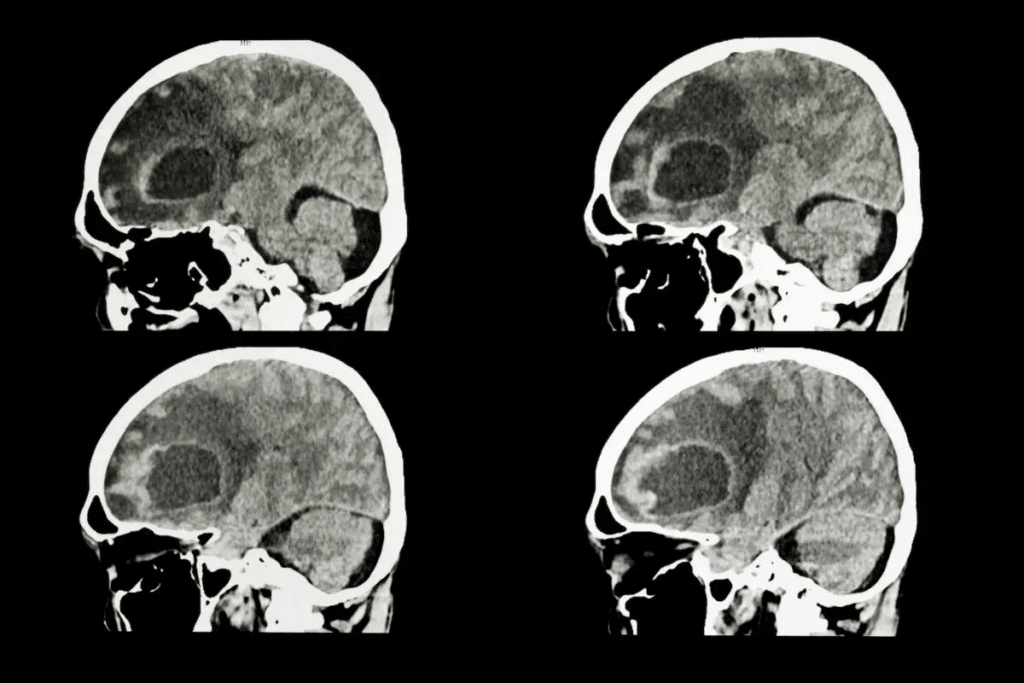

Diagnostic Approaches for Metastatic Brain Tumors

Diagnosing metastatic brain tumors requires imaging, biopsies, and molecular tests. Getting the diagnosis right is key for good treatment plans.

Imaging Techniques

Imaging is vital for spotting metastatic brain tumors. The main tools used are:

- Magnetic Resonance Imaging (MRI): MRI is top-notch for finding brain metastases, thanks to contrast agents like gadolinium.

- Computed Tomography (CT) scans: CT scans are faster and easier to get than MRI but miss smaller metastases.

- Positron Emission Tomography (PET): PET scans, paired with CT or MRI, offer metabolic insights into tumors.